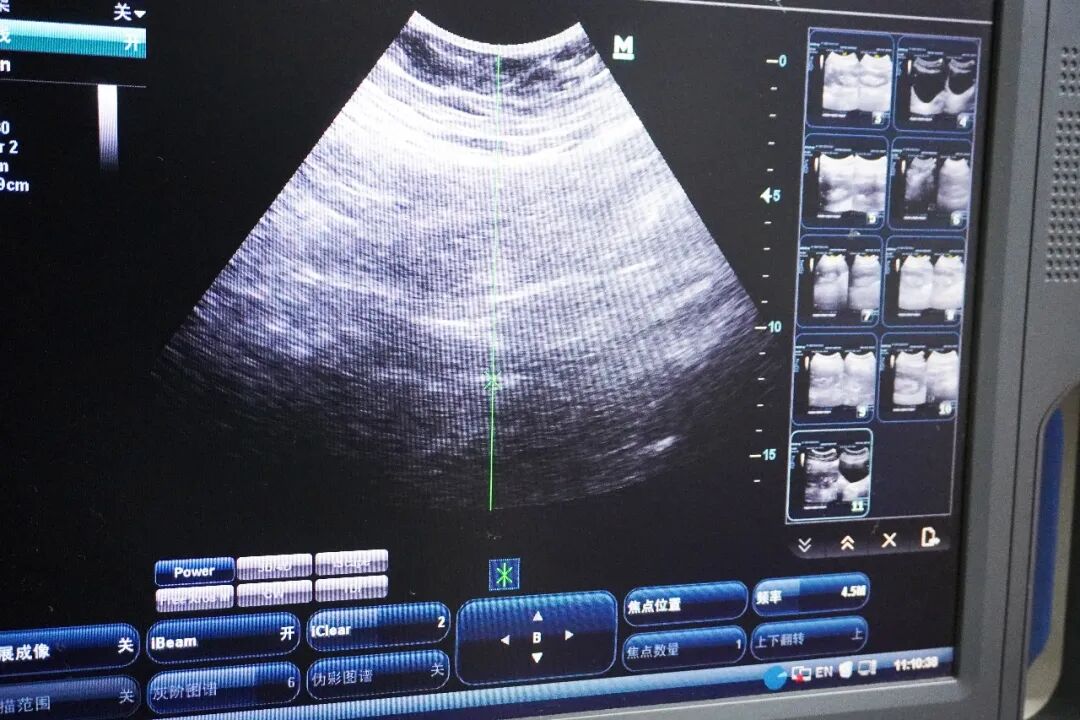

手术当日,在完备的麻醉与监护下,主刀医师娴熟地将纤细的输尿管软镜置入。通过高清成像系统,结石情况在显示屏上清晰呈现。随后,医师将钬激光光纤通过软镜的工作通道送至结石处。钬激光具有“碎石能力强、组织穿透浅、出血风险低”的特性,在水的介质中能将结石高效粉碎成细沙状或微小颗粒。手术团队凭借经验与稳定操作,逐步将梗阻在肾盂出口的结石彻底粉碎。为保障术后引流通畅、促进残留微粒排出、防止输尿管水肿狭窄,团队同期为患者置入了输尿管支架管。整台手术过程流畅,出血少,成功解除了肾脏梗阻,大程度保护了肾单位功能。